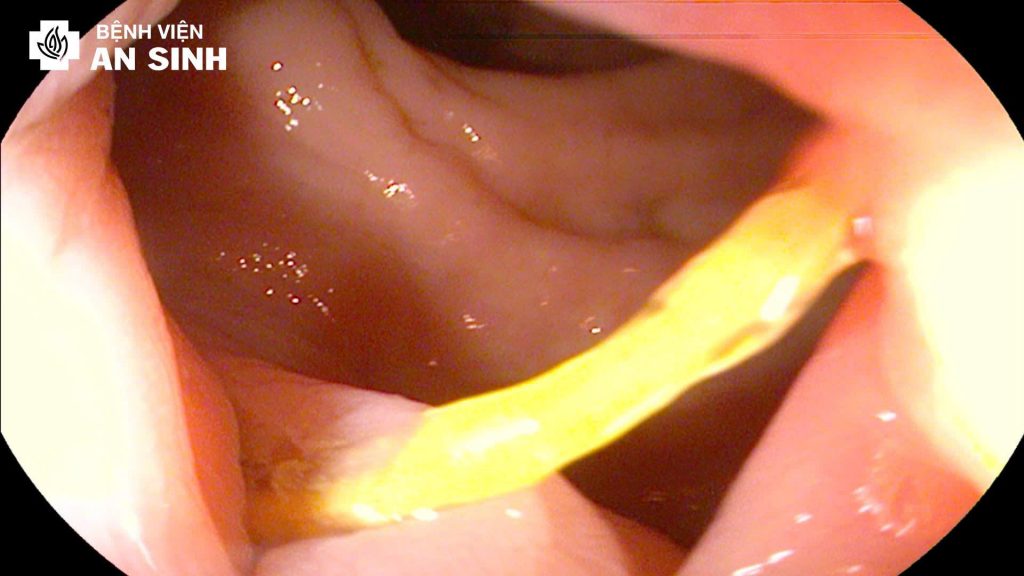

Kết quả thăm khám cho thấy cơ vòng hậu môn đóng kín, đồng thời có nhiều búi trĩ nội sa ra ngoài. Khi nội soi trực tràng – đại tràng, êkip ghi nhận một dị vật là xương cá sắc nhọn, dài khoảng 2cm, nằm cách bờ hậu môn 3cm và cắm một đầu vào thành trực tràng.

Trước tình trạng nguy cơ, êkip do BS.CKI Đoàn Văn Thuyên tiến hành nội soi can thiệp để gắp dị vật. Bệnh nhân được đặt ở tư thế nghiêng trái, sau đó bác sĩ sử dụng kìm chuyên dụng để tiếp cận và lấy xương cá ra ngoài qua đường nội soi.